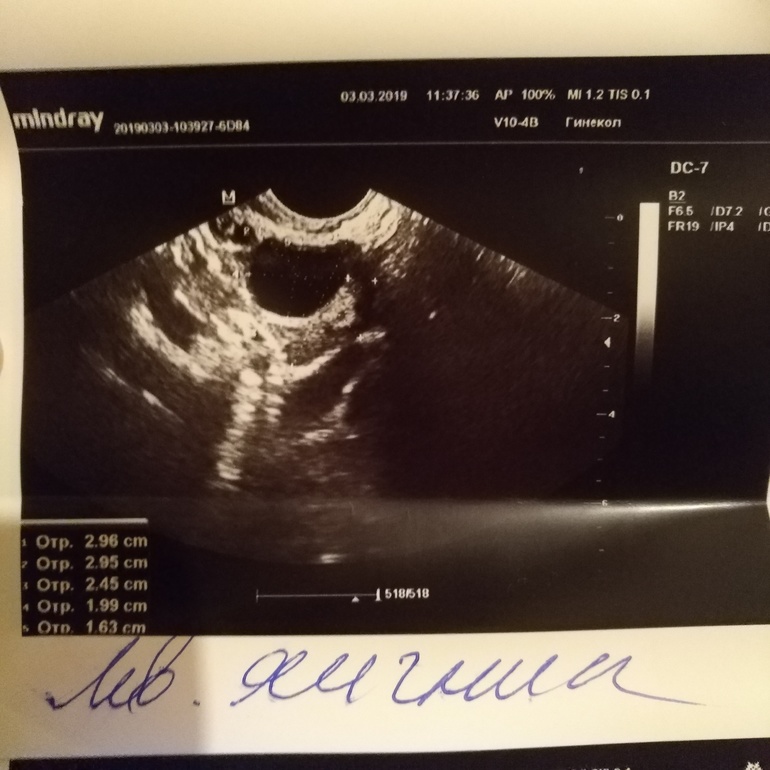

Похоже что персистенция фолликула. Так как размер почти 3 см. Для доминантного очень много

Я тоже это подозреваю. Т.к. эндометрий был на 12д.ц. 12 мм, тесты на лг были отрицательными, а в прошлом цикле была задержка на 4 дня. А может в другом яичнике в этом цикле созреть фолликул? Возможно такое?

Нет. Это маловероятн. Что киста ЖТ что перстинтентеый фолликул. Выделяет прогрестерон. А при прогрестероне, созревание нового фолликула и овуляция маловероятно

А на что это должно быть похоже? Написано же левый яичник. Вам что исследовали?